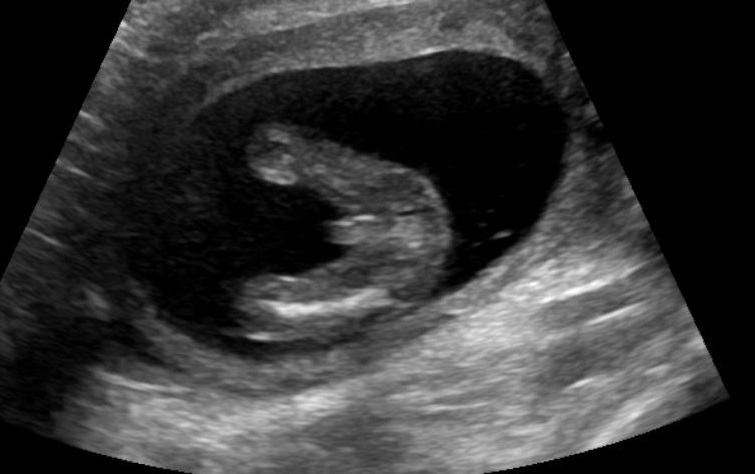

These all looks boy shots don't they, I'm in denial & clutching at straws here after trying for a girl ... Looks like 3 boys for us !

Forgot to mention measuring 15 weeks 3 days